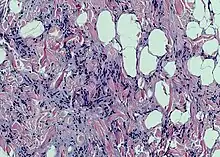

| Spindle cell lipoma | |

Spindle cell lipoma is an asymptomatic, slow-growing subcutaneous tumor that has a predilection for the posterior back, neck, and shoulders of older men.[1]: 625 [2]